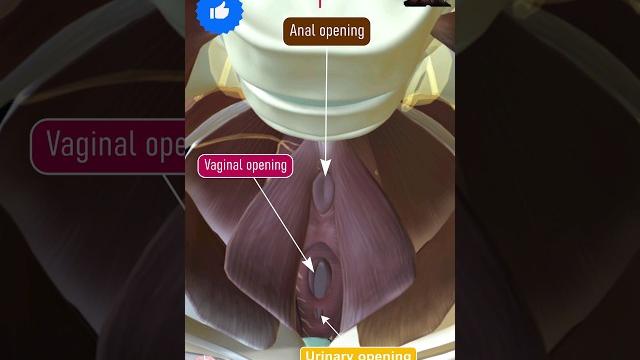

Girl pelvic

Для вашего запроса найдены видео: Guided meditation for pelvic floor relaxation | femfusion fitness, Best exercises for prolapse and bladder leaks safely strengthen your pelvic floor!, Clinical pelvimetry